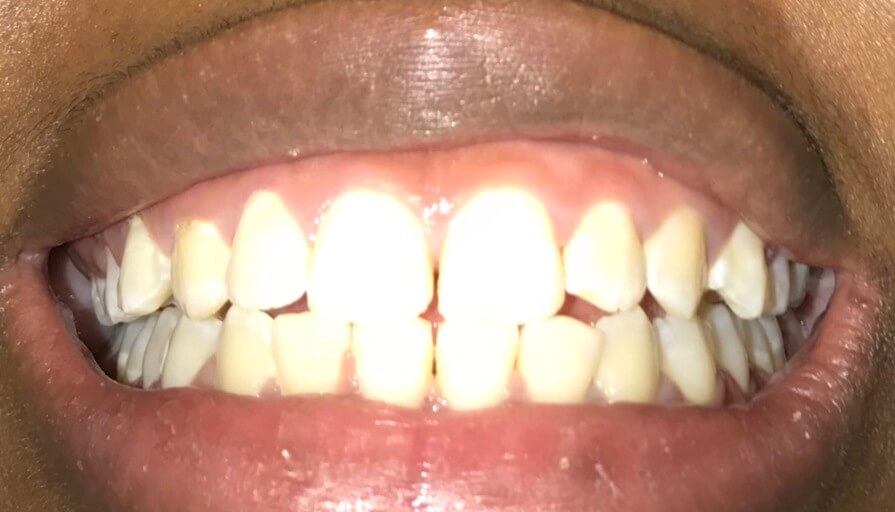

Hi I’ve been having issues with my jaws the feeling of them being extremely sore and I also cannot bite completely down on one of my sides of my mouth my teeth don’t look perfect or good they look “normal” I guess you can call it what would fix this ? Do I need braces ? My friends tell me I have a slight overbite but I can’t physically tell and I also bite the sides of my mouth and the inside of my lip a lot while eating.. what should I do ? I go to the dentist soon but is it best for me to go to a dentist or orthodontist?

From the picture submitted, it appears that you are biting edge to edge, which does need to be addressed and corrected by your orthodontist. It is ideal to mention these symptoms to your dentist at your check up appointment. Your jaw should not be sore on a regular basis. This could be a symptoms of a dysfunctional temporomandibular joint (TMJ). While the small spaces are more cosmetic, the uneven bite, soreness and inability to completely close on one side all raise red flags. Its best to correct these issues now, rather than to wait for them to worsen or for restorative treatment to be needed in addition to orthodontics due to wear patterns.